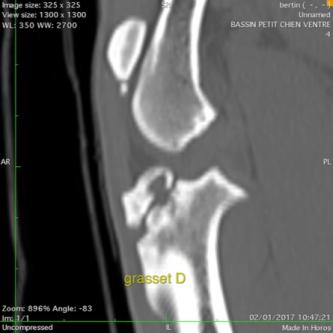

Les AUTRES SCANNER

Le scanner est utilisé dans les bilans d'extension de tumeurs mais pas que ... l'examen sert aussi à rechercher n'importe quel type de lésion dans les tissus mous et les articulations.

Ancienne fracture tuberosité tibiale